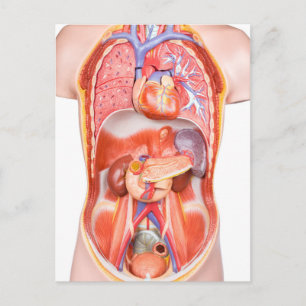

Anatomi i mänskliga organ vykort

Pris23,00 kr

Anatomi i mänskliga organ poster

Pris229,00 kr

Anatomi i mänskliga organ canvastryck

Pris1 425,00 kr

Anatomi i mänskliga organ hälsningskort

Försäljningspris 49,00 kr. Ursprungligt pris 54,00 kr.